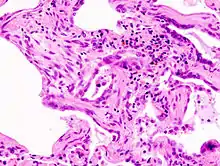

Coloration à l'hématoxyline et à l'éosine (HE).

L'interstitium (tissu de soutien) du poumon est constitué de septums interalvéolaires, situés entre les parois des alvéoles pulmonaires. Ces dernières, siège de l'échange gazeux entre sang et air, forment le tissu proprement fonctionnel du poumon (parenchyme). L'interstitium et le parenchyme coopèrent étroitement au fonctionnement du poumon, et constituent une unité fonctionnelle. L'interstitium constitue l'armature de base du poumon et soutient l'architecture des alvéoles, c'est-à-dire de la barrière sang-air pendant le cycle de la respiration. Cet interstitium est constitué de cellules, avant tout spécialisées dans le soutien (fibroblastes), de protéines structurales qu'elles produisent, et en substances telles que le collagène, les fibres élastiques, les protéoglycanes ainsi que d'autres glycoprotéines.